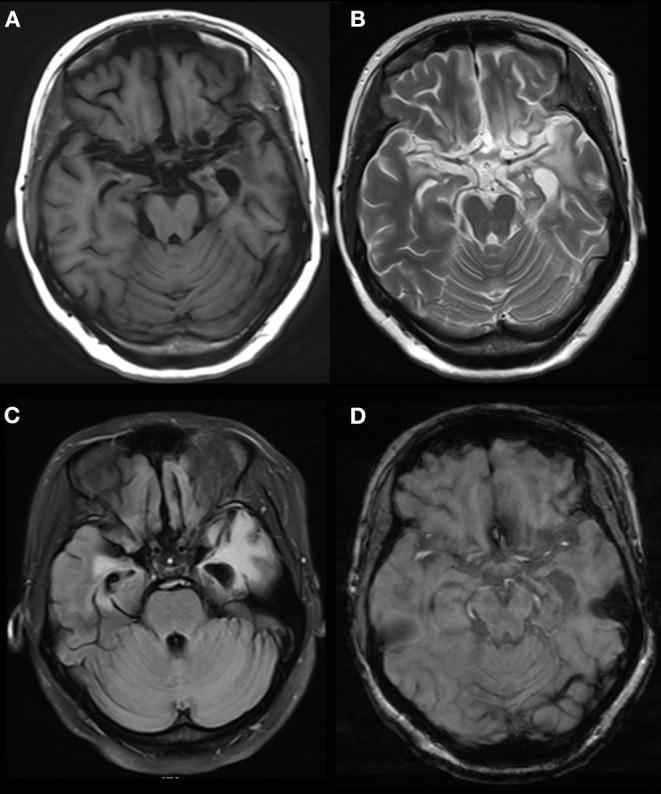

Anti-GABA-B (gamma aminobutyric acid-B) receptor encephalitis is an autoimmune disease mediated by GABA-B-related antibodies. To fully understand the disease, we collected clinical data from patients with GABA-B receptor encephalitis and conducted an analysis to draw conclusions. All patients with GABA-B receptor encephalitis from the Neurology Department of Beijing Tiantan Hospital, affiliated with Capital Medical University, from August 2015 to September 2019 were accepted as study subjects. The clinical data of the patients were analyzed retrospectively and included the general demographic characteristics, clinical manifestations, and auxiliary examinations, including laboratory results, electroencephalograms (EEGs), brain magnetic resonance imaging (MRI), and positron emission tomography (PET-CT) results, as well as treatments. From August 2015 to September 2019, 14 cases of anti-GABA-B receptor encephalitis were diagnosed. Among these patients, middle-aged and elderly men were the main demographic, with an average age of 52 years; moreover, the onset of the disease was relatively sudden, and the time from onset to diagnosis was ~1 month. The main clinical symptoms were frequent epileptic seizures, cognitive dysfunction, and mental behavioral disorders. In seven (50%) patients, the leukocyte in cerebrospinal fluid (CSF) were increased. Five (36%) patients had elevated cerebrospinal fluid protein. In most patients, the oligoclonal bands (83%) of CSF were positive, and 24 h IgG levels (92%) were increased. Anti-Hu or anti-Yo antibodies were positive in two (14%) patients. Tumor markers in 10 (71%) patients indicated that neuron-specific enolase, gastrin-releasing precursor, non-small cell lung cancer-related antigen, or carcinoembryonic antigen levels were increased. EEG results often indicated slow waves, sharp waves, or spike waves in temporal areas. Brain MRI always showed high T2 signals in the medial temporal lobe, hippocampus, and amygdala and swelling in the medial temporal lobe and hippocampus. PET-CT scans almost showed abnormal metabolism in the hippocampus and temporal lobe. Three (21%) patients who underwent systemic PET-CT showed hypermetabolism in pulmonary parenchymal nodules and enlargement of mediastinal lymph nodes. All patients underwent high-dose hormone therapy or immunoglobulin immunotherapy. After treatment, the symptoms of epilepsy, cognitive disorders, and mental behavioral disorders improved to varying degrees. However, one patient died of lung cancer. Anti-GABA-B receptor encephalitis mainly occurred in middle-aged and elderly men, and the disease onset was relatively sudden. Before disease onset, some patients experienced fever and non-specific respiratory symptoms, which mainly manifested as frequent epileptic seizures, cognitive dysfunction, and abnormal mental behavior. MRI and PET-CT revealed abnormal signals and local metabolism, respectively, in the temporal lobe. Moreover, the disease has a close relationship with lung cancer, which requires long-term follow-up observation.

抗GABA - B(γ-氨基丁酸B)受体脑炎是一种由GABA - B相关抗体介导的自身免疫性疾病。为全面了解该疾病,我们收集了GABA - B受体脑炎患者的临床资料并进行分析以得出结论。2015年8月至2019年9月首都医科大学附属北京天坛医院神经内科的所有GABA - B受体脑炎患者均被纳入研究对象。对患者的临床资料进行回顾性分析,包括一般人口统计学特征、临床表现及辅助检查,后者包括实验室检查结果、脑电图(EEG)、脑磁共振成像(MRI)、正电子发射断层扫描(PET - CT)结果以及治疗情况。2015年8月至2019年9月,共诊断出14例抗GABA - B受体脑炎患者。这些患者中,中老年男性为主,平均年龄52岁;疾病起病相对突然,从起病到诊断的时间约为1个月。主要临床症状为频繁癫痫发作、认知功能障碍及精神行为障碍。7例(50%)患者脑脊液(CSF)白细胞增多。5例(36%)患者脑脊液蛋白升高。大多数患者CSF的寡克隆带(83%)呈阳性,24小时IgG水平(92%)升高。2例(14%)患者抗Hu或抗Yo抗体呈阳性。10例(71%)患者的肿瘤标志物显示神经元特异性烯醇化酶、胃泌素释放前体、非小细胞肺癌相关抗原或癌胚抗原水平升高。EEG结果常显示颞叶有慢波、尖波或棘波。脑MRI总是显示内侧颞叶、海马和杏仁核T2信号增高以及内侧颞叶和海马肿胀。PET - CT扫描几乎均显示海马和颞叶代谢异常。3例(21%)接受全身PET - CT检查的患者显示肺实质结节代谢增高及纵隔淋巴结肿大。所有患者均接受了大剂量激素治疗或免疫球蛋白免疫治疗。治疗后,癫痫、认知障碍及精神行为障碍症状均有不同程度改善。然而,1例患者死于肺癌。抗GABA - B受体脑炎主要发生于中老年男性,起病相对突然。发病前部分患者有发热及非特异性呼吸道症状,主要表现为频繁癫痫发作、认知功能障碍及精神行为异常。MRI和PET - CT分别显示颞叶有异常信号及局部代谢异常。此外,该疾病与肺癌关系密切,需要长期随访观察。